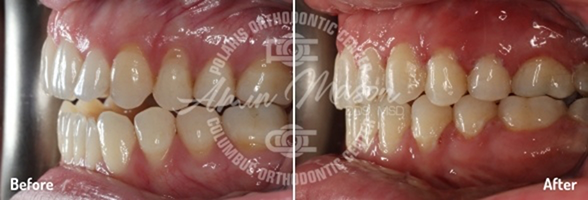

Case 6

A 23-year-old female patient presented to our office with severe crowding and worn teeth. The patient was not happy with the appearance of the teeth and the shape of the restoration on tooth #9. The patient was treated with extraction of 4 premolar teeth and the Damon system in 20 months. She will undergo whitening and restoration of tooth #9 for improved aesthetics.